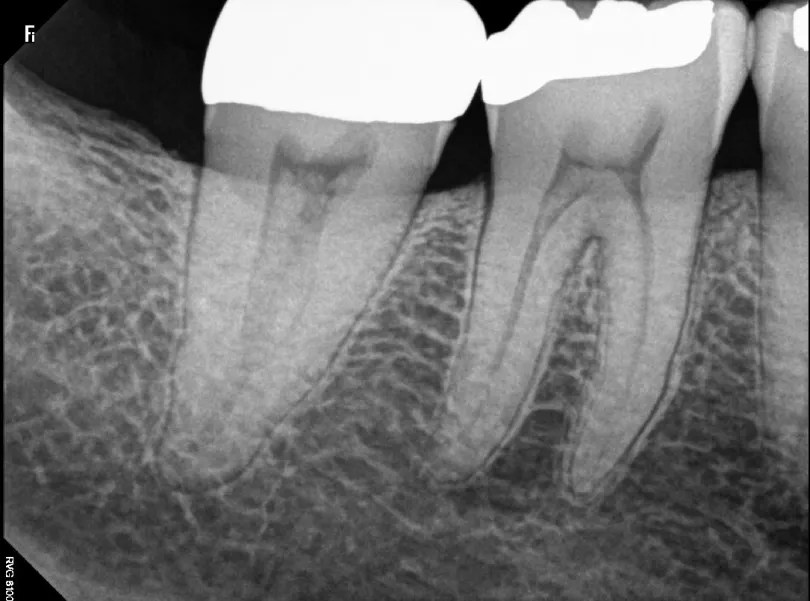

Single teeth X-rays

Single teeth X-ray is an image of a tooth depicted from the crown to the point where it joins the jaw. It usually takes two or a portion of your teeth either from the upper or lower jaw. Single tooth X-ray gives valuable information on root health by showing any abnormal tissue changes